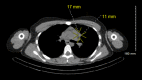

The classic clinical vignette of primary hyperparathyroidism is well described as "bones, stones, abdominal moans, and psychiatric overtones" to reflect the effects of excess parathyroid hormone (PTH) and calcium. Most commonly, primary hyperparathyroidism is due to a functional parathyroid adenoma situated by the thyroid gland. Rarely, the primary focus of autonomously produced PTH is located ectopically within the mediastinum. A 19-year-old Caucasian female with no relevant past medical history presented to the emergency department with tachycardia, nausea, vomiting, and a five-day history of vague, mid-abdominal pain. Initial computed tomography (CT) with contrast of the abdomen and pelvis was negative for acute findings, and she subsequently underwent biochemical screening. The patient was found to have elevated serum calcium and PTH, raising suspicion for the diagnosis of primary hyperparathyroidism. Further evaluation for a parathyroid adenoma was negative by a CT scan of the neck and thyroid ultrasound. A nuclear medicine parathyroid single-photon emission computed tomography (SPECT)/CT with technetium (Tc) 99m sestamibi found an abnormal nodular uptake within the left prevascular mediastinum suggestive of an ectopic parathyroid adenoma. A left-sided, video-assisted thoracoscopic surgery (VATS) with successful excision of the ectopic mediastinal parathyroid adenoma was performed. Surgical pathology revealed that the parathyroid adenoma was completely excised and surrounded by thymus and adipose tissue. The patient tolerated the procedure well and was discharged without further complications. The rarity of mediastinal, intrathymic parathyroid adenomas resulted in delayed diagnosis in this patient, understandably so as errant embryogenesis does not occur commonly. Visualization with SPECT/CT and successful specimen excision by minimally invasive VATS resulted in the accurate diagnosis and ultimate cure of this patient's primary hyperparathyroidism.